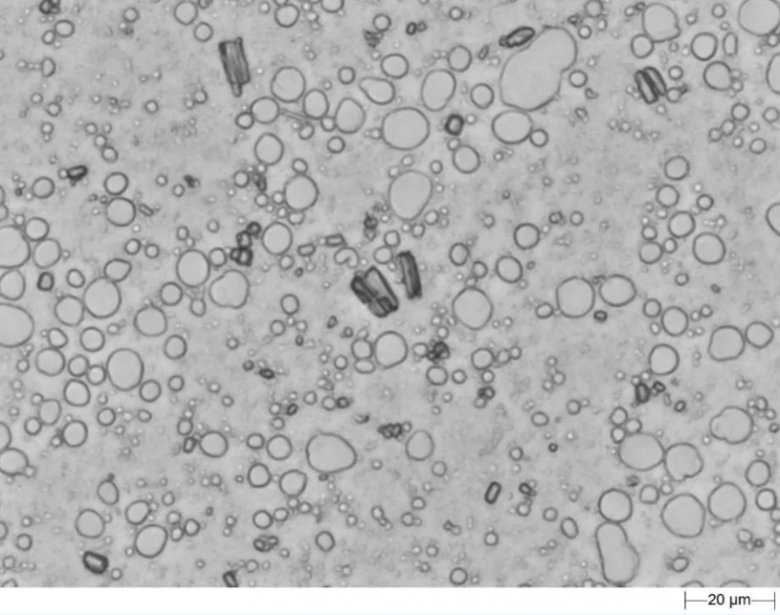

采用“三明治”制样法,通过Morphologi 4自动扫描分析,二十分钟之内即可获得API颗粒和液滴颗粒的粒径分布结果,以及API的晶癖和液滴颗粒的圆度值等形貌因子的分布值。

混悬型乳膏剂

Morphologi 4 自动扫描乳膏剂样品